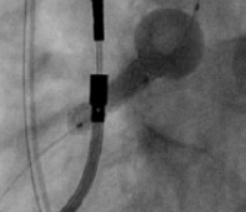

TRUE 360° FLARED APPOSITION

Novel 2-in-1 dual balloon design allows for inflation of a non-compliant distal balloon to anchor the system, while inflation of the compliant, low-pressure proximal balloon conforms the stent to the wall of the ostium.

Excellent Final Result

RCA Ostial Stenosis

Post-dilatation with FLASH

TRUE 360° result